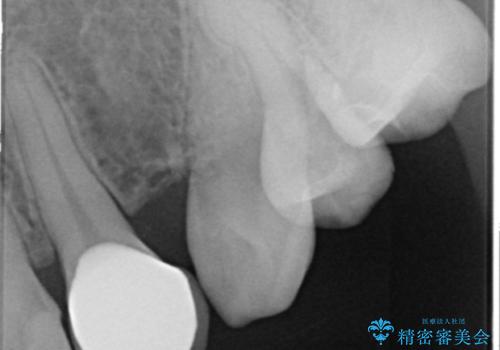

- 上の前歯の色と隙間を気にされ、来院された患者様です。

精査したところ、右上の側切歯(右上2)は神経が死んで変色しており、左上の側切歯と犬歯の間に2mm程度の隙間を認めました。

矯正せずに早く治したいという強いご希望により、セラミッククラウンによる補綴治療(上顎両側2の2本)を行いました。